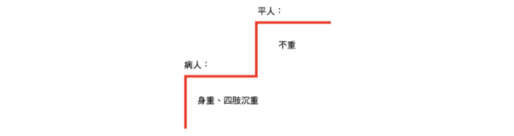

當綜覽《傷寒論》中各種類型的「身重」之病後,將可發現舉凡「身重」、「四肢沉重」等疾病症狀,均是身體的異常感受。由此可知,相對於病中異常的「身重」之感,未病的平人所感受的理當是「不重」、較為輕鬆的身體感。

《傷寒論》中身「重」之病的身體感圖解

《傷寒論》中身「重」之病的身體感圖解